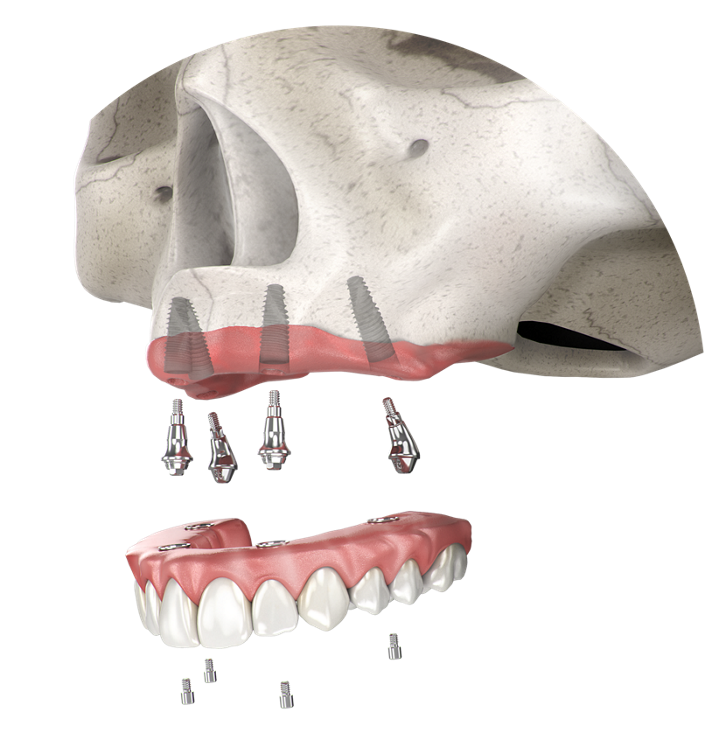

NeoArch

El Sistema de Implantes NeoArch® de Neodent® ofrece una solución optimizada para protocolos de tratamiento de arco fijo inmediato para pacientes edéntulos, incluso en casos con maxilares severamente atróficos.

NeoArch® está diseñado para aumentar la satisfacción del paciente y la calidad de vida al restaurar inmediatamente la función y la estética.

Solución para arcada completa

Tecnología del Sistema Grand Morse®

Concepto de Cuerpo Helix®

Muñón Cónico Mini